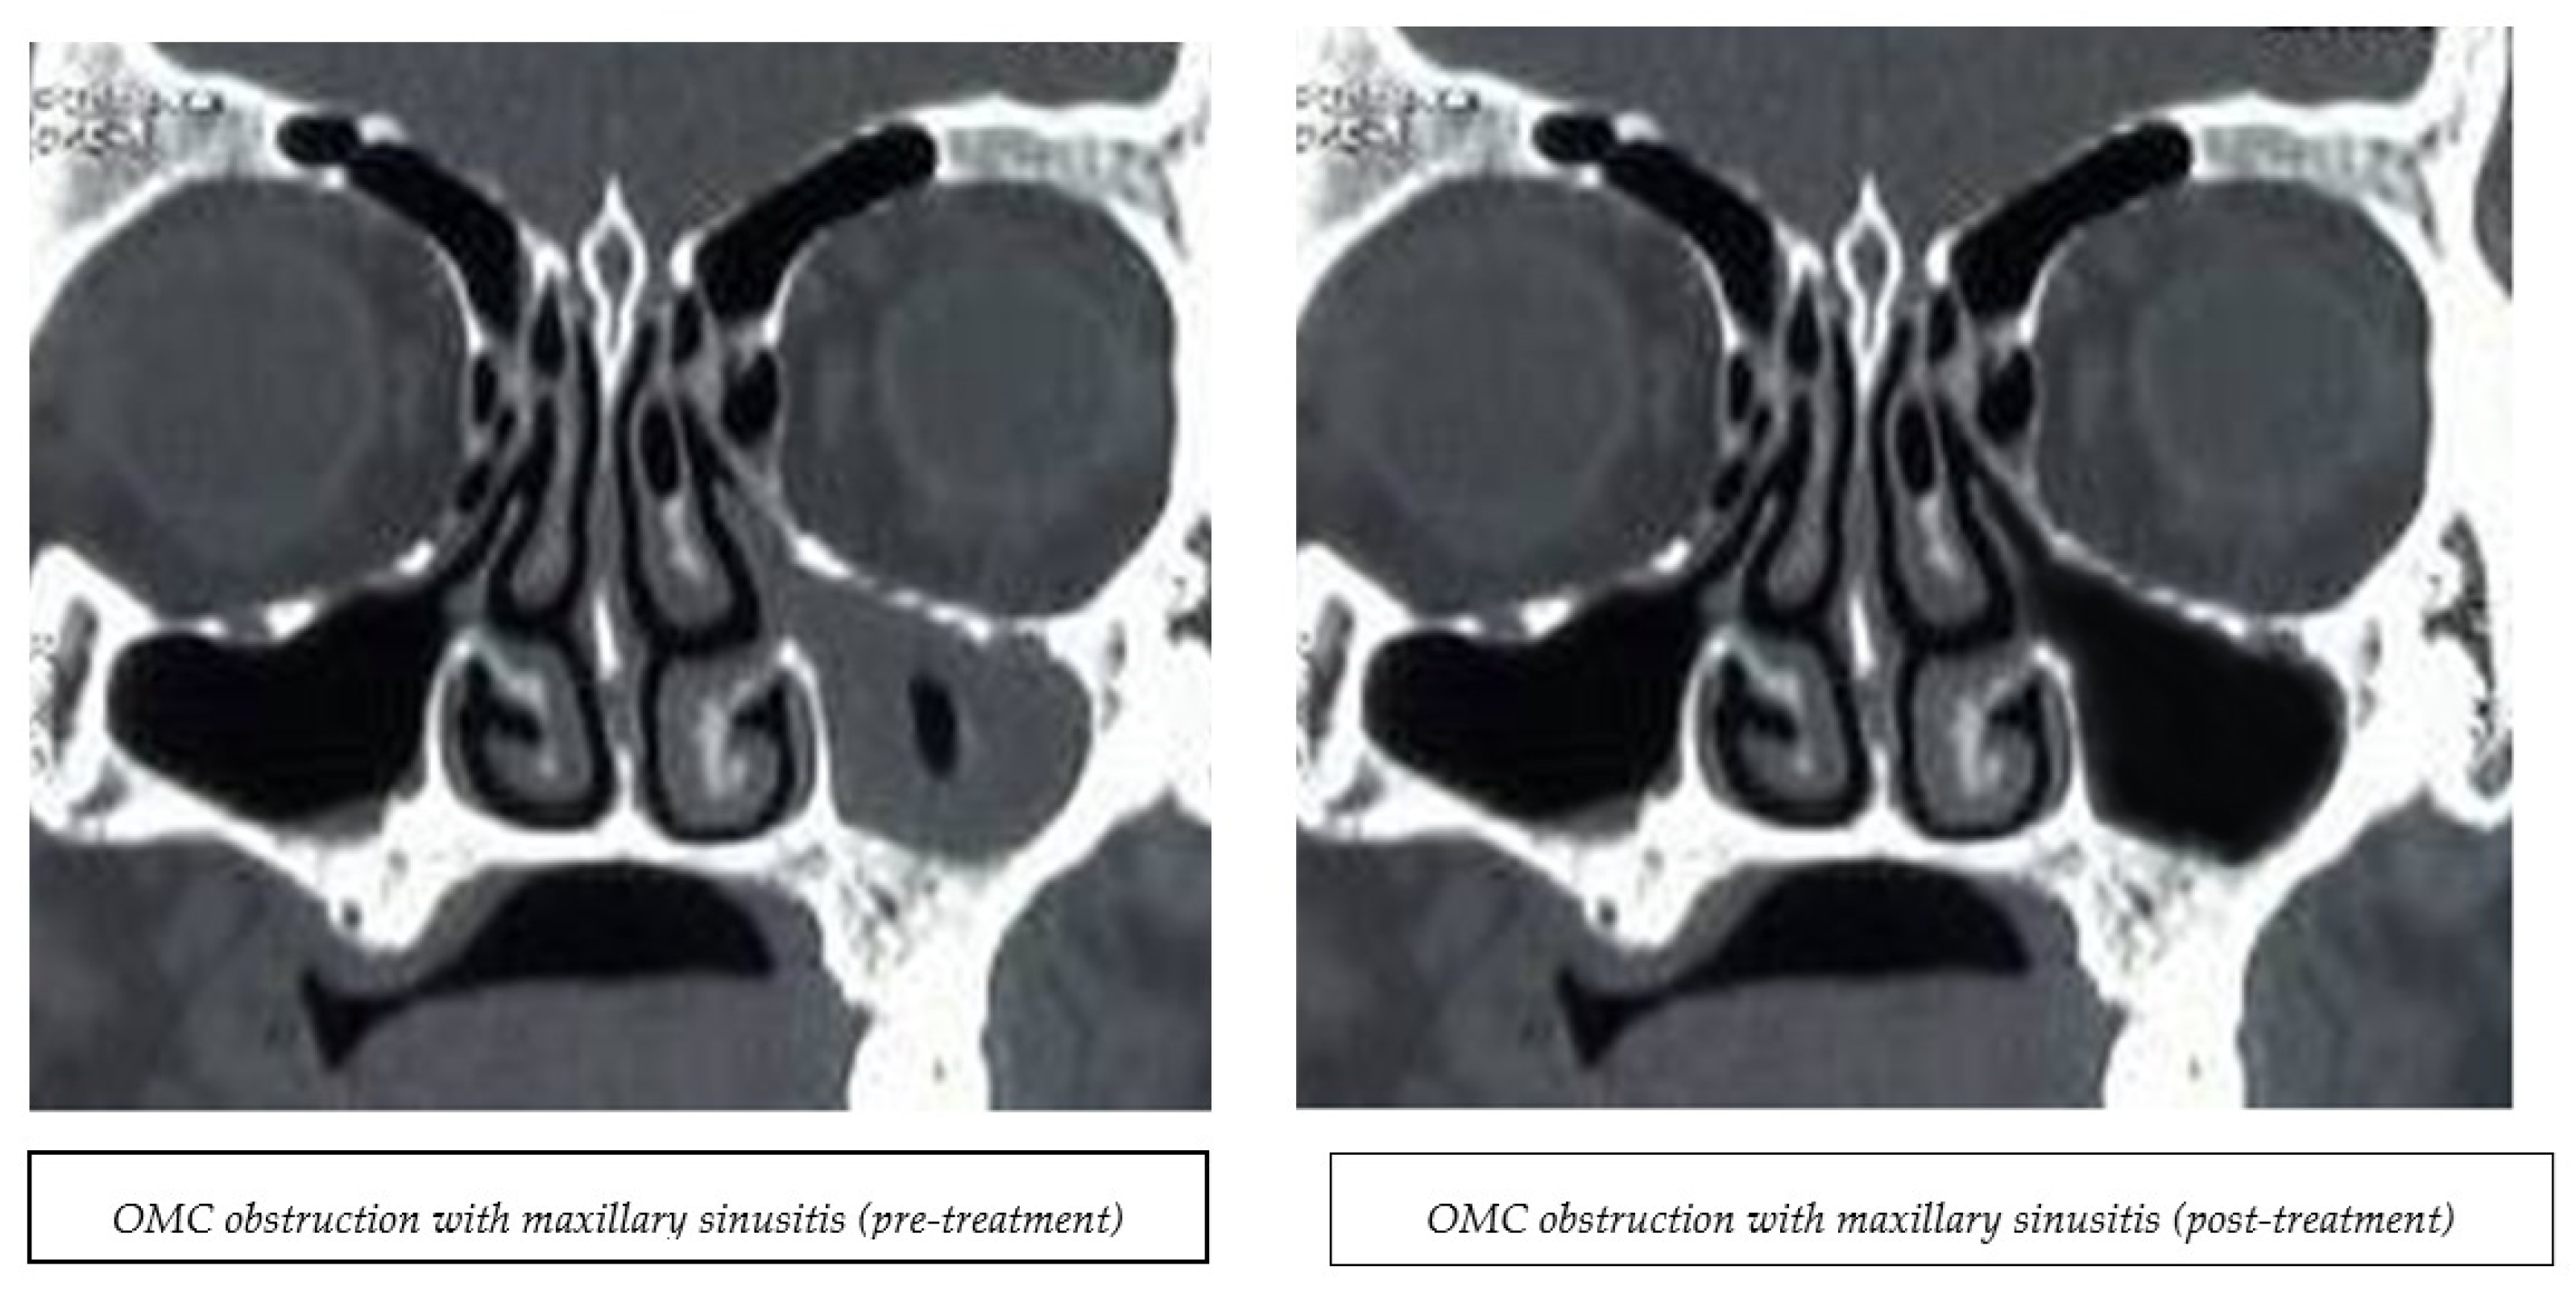

Computerized tomography scanning examinations were conducted at a radiological center before and after the treatment’s completion. The results obtained from the CT films revealed sinus opacification and ostiomeatal complex obstruction. Figure 2 displays the CT findings’ pre- and post-values. The Lund–Mackay score was assessed before and after the study’s completion.

Figure 2.

Pre- and post-CT findings after EMFT treatment.

3.6. Sinus Opacification and Ostiomeatal Obstruction

The data in Table 3 show no significant difference (p > 0.05) between the two groups in the number of opacities in the ethmoid, sphenoid, frontal, and maxillary sinuses before treatment. Following treatment, both groups had no significant difference in the opacification of the right (RT) and left (LT) ethmoid sinuses. However, the PEMF group demonstrated a notable improvement, with 75% of the Rt and Lt opacified ethmoid sinuses clearing up, in contrast to the 0% observed in the control group. A significant proportion of the Rt sphenoid sinuses (66.6%) exhibited complete resolution in the PEMF group compared to the control group. Compared to the control group, the Lt opacified sphenoid sinuses were completely cured in the PEMF group, which showed no disappearance of the opacified sphenoid sinus (p = 0.045). In the PEMF group, the resolution of the Rt and Lt opacified frontal sinuses was observed, despite the non-significance level (p = 0.243). For the maxillary sinuses, a highly significant difference was present between the groups compared to the control group; all Rt and Lt maxillary sinuses showed complete recovery in the PEMF group (p = 0.007).

The CT findings indicated that magnetic therapy application reduced sinus opacification and decreased the opacity of all sinuses. This effect was highly predominant in the left sphenoid sinus, right maxillary sinus, and left maxillary sinus, which might have been due to the variation in sinus volume. This study found that magnetic field therapy effectively cleared up the ostiomeatal blockage for the frontal, maxillary, and ethmoid sinuses. Clearance of the ostiomeatal blockage made fluid flow through the sinuses easier, reducing headaches. It is well known that the inflammatory process in CRS leads to obstruction of the ostiomeatal complex (OMC) and vice versa, resulting in impaired nasal patency due to the concerted bacteria and foreign bodies at the nasal/sinus interface, affecting pH, mucociliary transport and clearance, air temperatures, and flow [43,44].